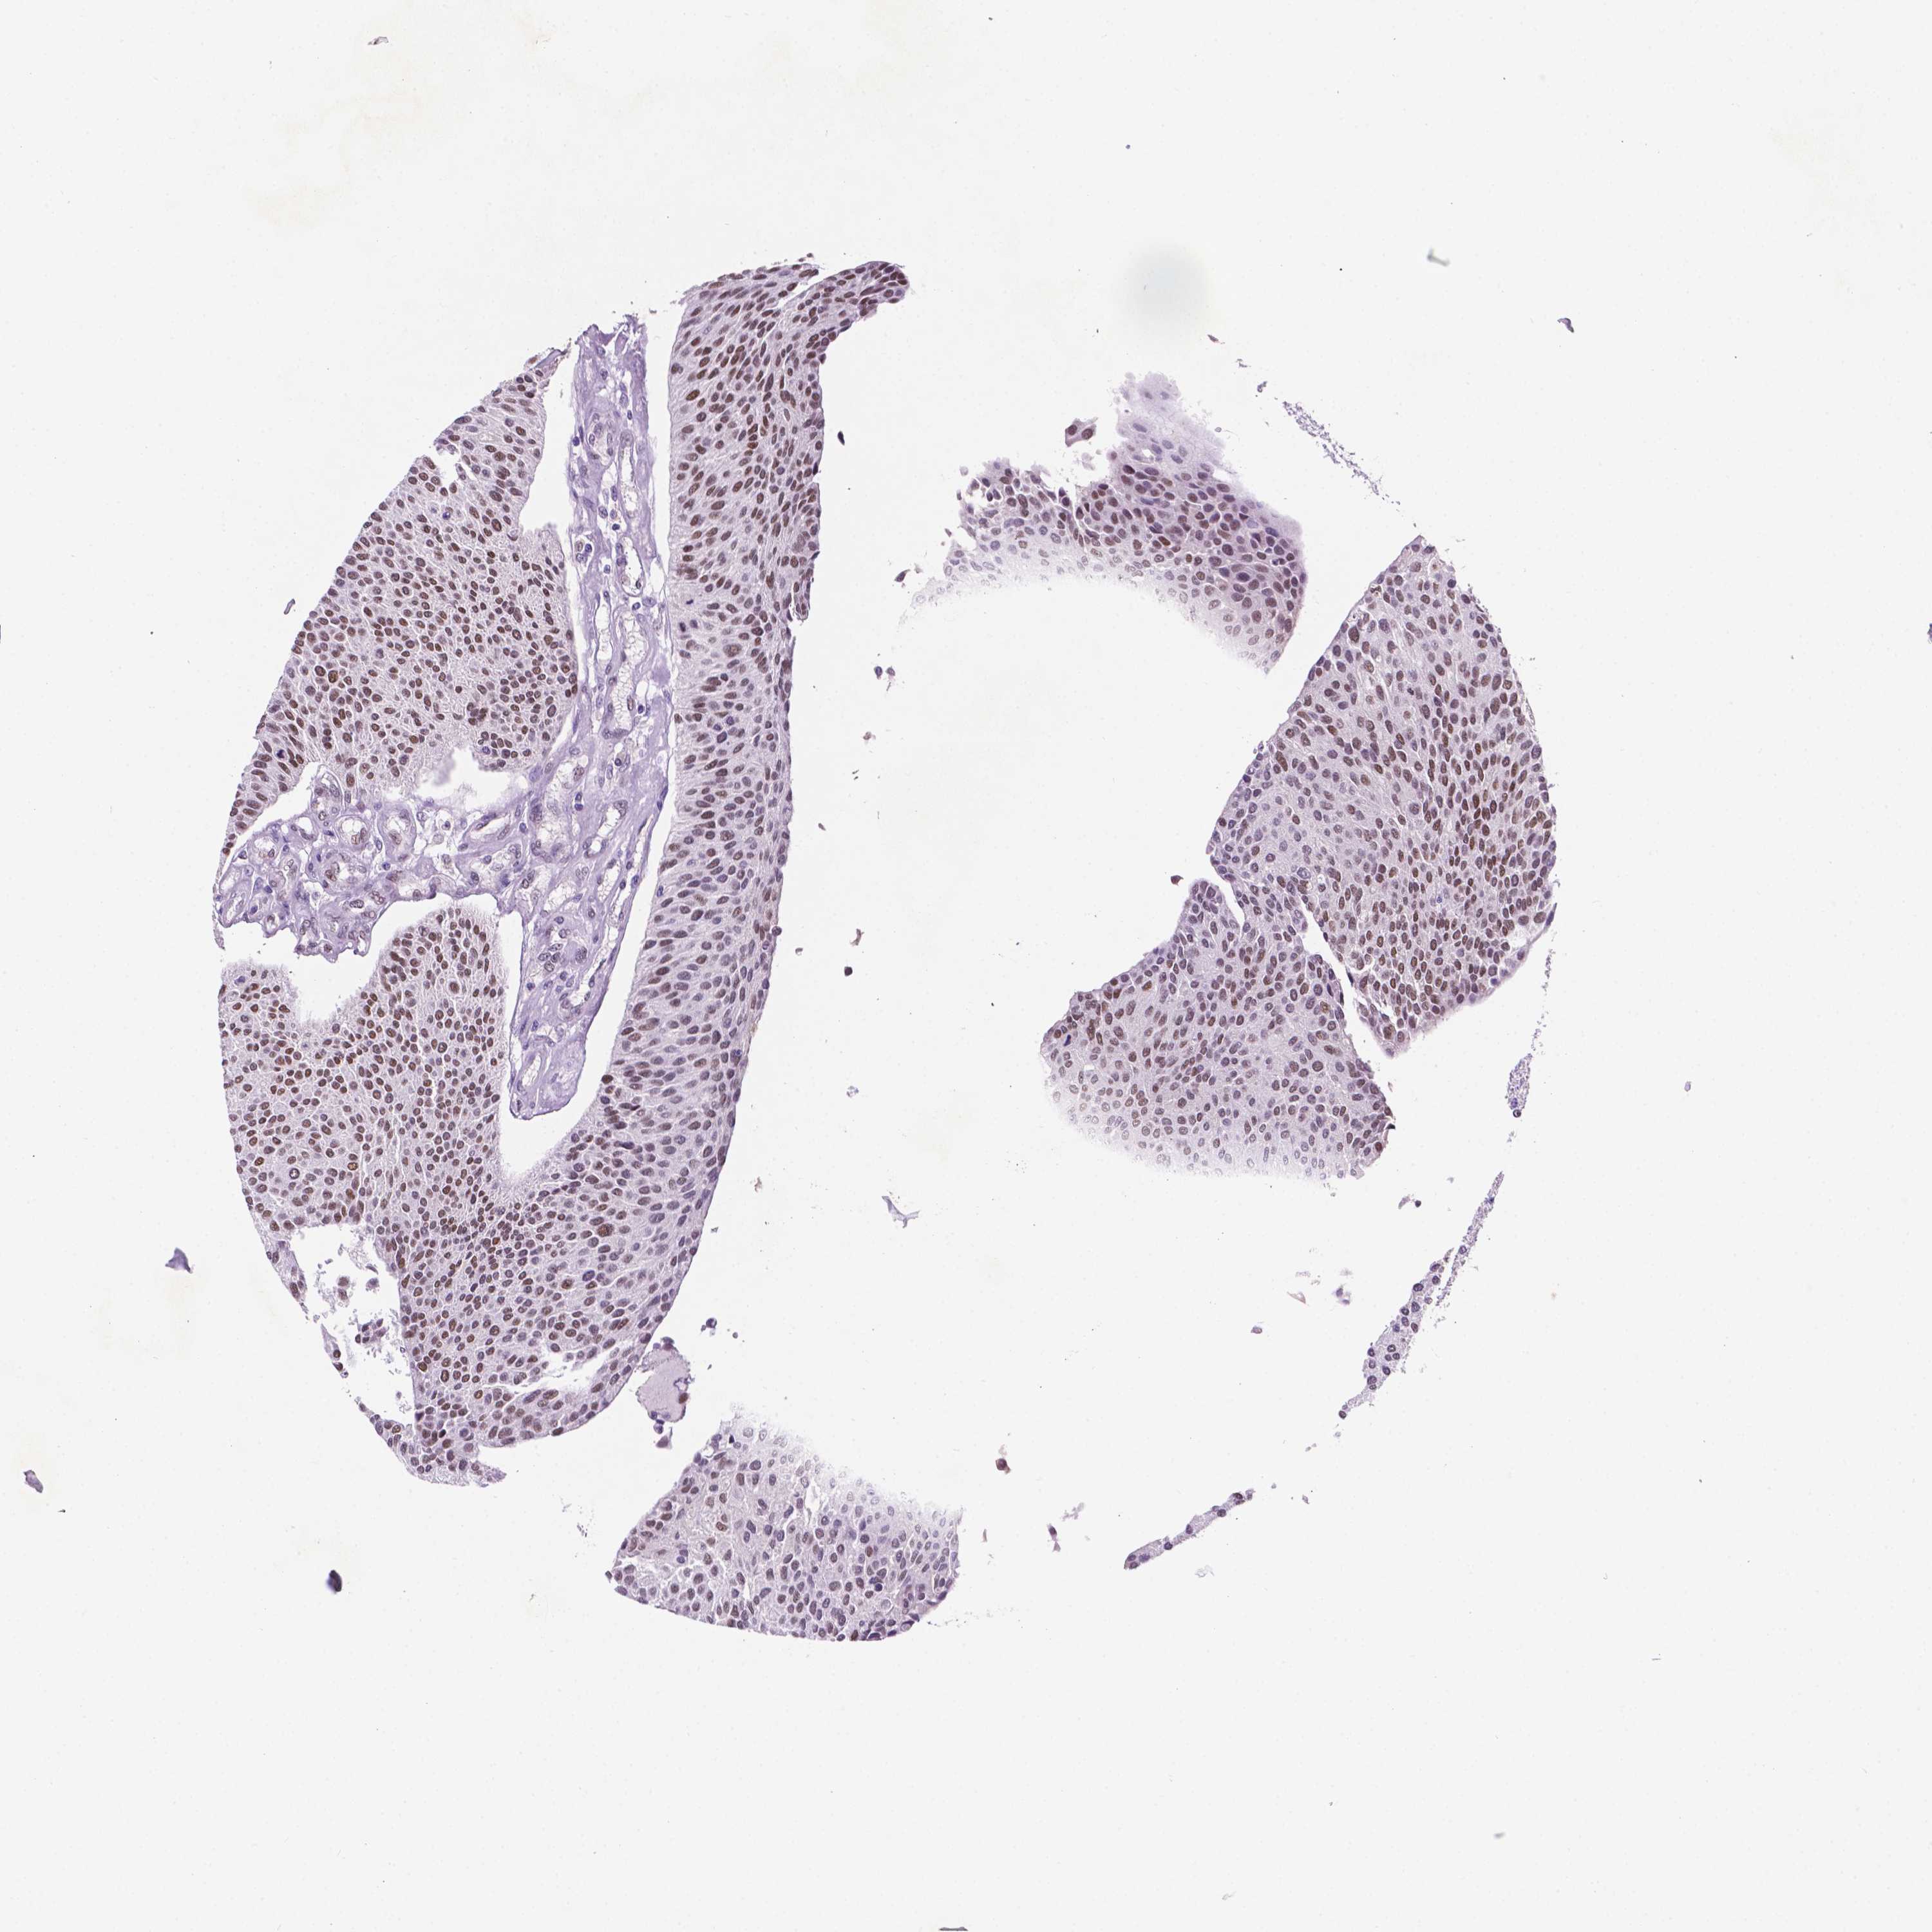

UROTHELIAL CANCER - Protein expressioni

A mouse-over function shows sample information and annotation data. Click on an image to view it in a full screen mode. Samples can be filtered based on level of antibody staining by selecting one or several of the following categories: high, medium, low and not detected. The assay and annotation is described here.

Antibody stainingi

Antibody staining in the annotated cell types in the current human tissue is reported as not detected, low, medium, or high, based on conventional immunohistochemistry profiling in selected tissues. This score is based on the combination of the staining intensity and fraction of stained cells.

Each image is clickable and will lead to virtual microscopy that enables deeper exploration of all samples and also displays staining intensity scores, fraction scores and subcellular localization as well as patient and tissue information for each sample.

Antibody HPA067952

Staining

High

Medium

Low

Not detected

Intensity

Strong

Moderate

Weak

Negative

Quantity

>75%

75%-25%

<25%

None

Location

Nuclear

Cytoplasmic/membranous

Cytoplasmic/membranous,nuclear

Urothelial carcinoma, High grade

Urothelial carcinoma, NOS

Urothelial carcinoma, Low grade